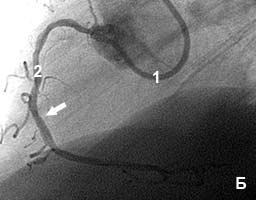

Пациент с жалобами на боли в сердце после незначительной физической нагрузки.

На коронарограмме (рис 5а) - субтотальный стеноз правой коронарной артерии.

В место стеноза установлен коронарный стент. Стеноз полностью устранен (рис.5б).

Боли прекратились сразу же после стентирования.

Рис.5 Стеноз правой коронарной артерии до (А) и после (Б) стентирования.

1 - катетер; 2 - контрастированная коронарная артерия; стрелкой отмечена зона стеноза. |